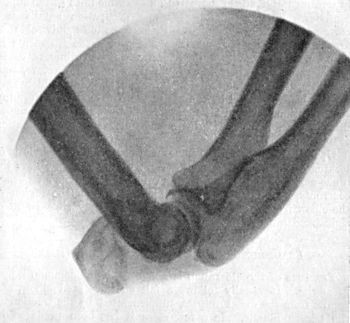

91 39.Forward Dislocation of Elbow, with Fracture of Olecranon

93 40.Radiogram of Forward Dislocation of Head of Radius, with Fracture of Shaft of Ulna